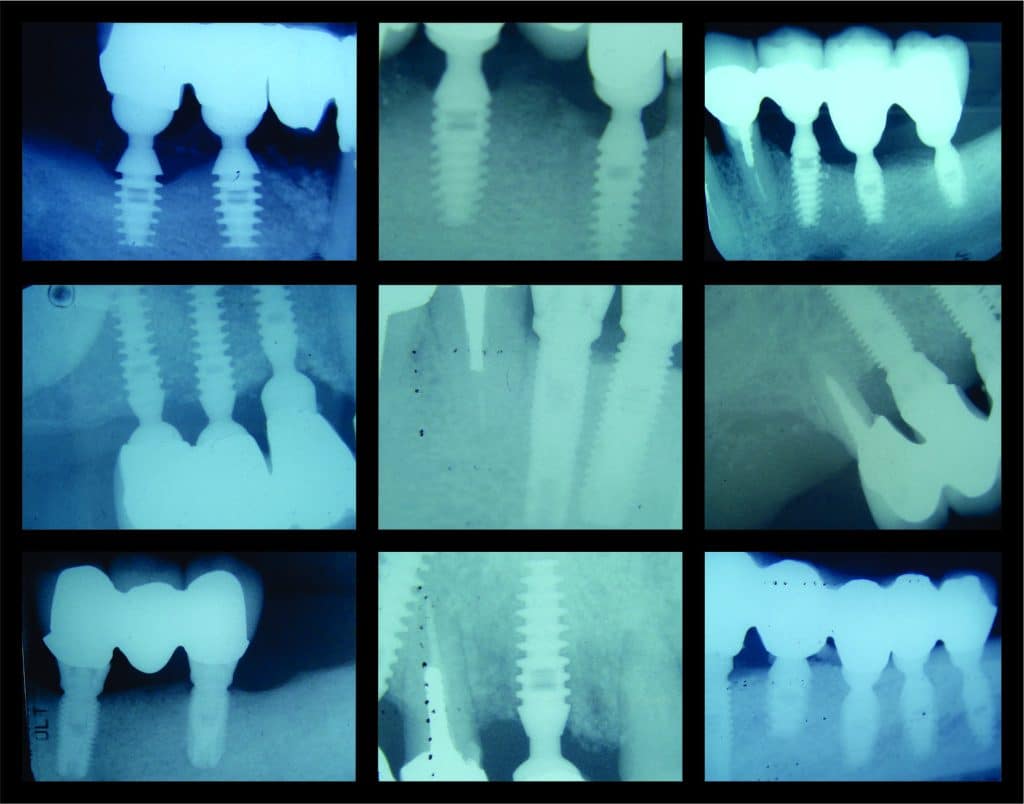

Are there different types of dental implants?

Are there different types of dental implants? There are several types of dental implants, each…